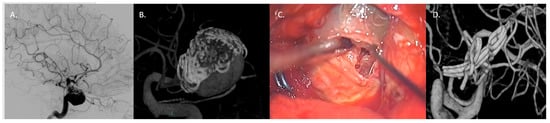

4.3.1. Large/Giant Aneurysm Size and Fusiform Shape

4.3.2. Vessels Branching from the Dome

4.3.3. Thrombosed Aneurysm and/or Previously Treated Aneurysms